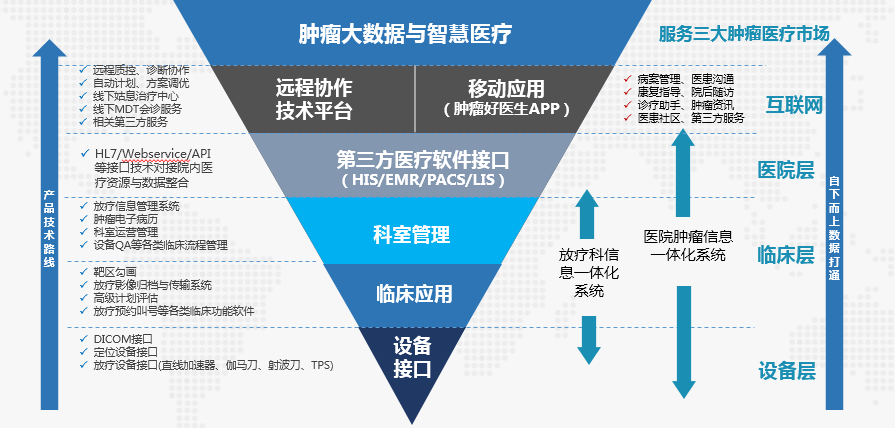

深耕肿瘤临床一线10余年的深圳hjc888黄金城�����,很早就最先了肿瘤大数据人工智能的妄想����。hjc888黄金城以为�����,在整个医疗数据里最深条理的一定是来自于装备层面�����,尤其是肿瘤放疗�����,治疗设惫亓数据是最基础最深层的数据�����,也是价值最高的医疗数据����。由此�����,hjc888黄金城花了许多年时间在装备层面上�����,把种种肿瘤治疗装备的数据接口买通�����,为肿瘤大数据的结构化融合以及基于深度学习的人工智能盘算平台搭建�����,涤讪了优异基础����。

首先�����,hjc888黄金城针对肿瘤治疗的临床治理历程提供了肿瘤信息一体化治理整体解决计划(OIS)�����,OIS是肿瘤信息化领域的综合产品系统�����,包括放疗信息治理(RTIS)系统、放疗勾画事情站、高级妄想评估(APE)系统、放疗纪录与验证(R&V)系统、放疗预约叫号系统、放疗妄想会诊系统等多个产品����。该产品舷笼罩了肿瘤治疗历程中方方面面�����,买通了肿瘤治疗所有装备的数据接口�����,实现了各环节营业数据无缝对接�����,为肿瘤治疗提供了一套实现科室规范化治理的信息化平台�����,医务职员可直接通过该平台举行肿瘤治疗历程治理和质量控制����。

其次�����,hjc888黄金城在实现医院内部肿瘤治疗信息化治理的基础上�����,针对肿瘤治疗周期长、医患互动频仍的特点�����,开发了一套用于医患治理效劳的移动医疗产品“肿瘤好医生”APP�����,与其他移动医疗产品差别的是�����,肿瘤好医生APP实现了从装备层、科室层、医院层、以及互联网层面的周全数据买通�����,形成了肿瘤治疗从预约、检查、诊断、治疗、随访、康复的周全数据闭环����。在APP上�����,患者在医院放疗的信息也会同步到APP�����,医生可以直接治理患者�����,患者也可以实时与医生交流����。

在实现单体医院的临床数据买通之后�����,hjc888黄金城最先了各医院之间的数据整合�����,通过互联网和云手艺�����,建设安诺云智@远程放疗协作平台平台�����,实现差别医院之间数据的互联互通�����,为落实国家关于医联体建设、开展远程医疗和分级诊疗提供专业化平台����。该平台充分使用了大数据和人工智能手艺�����,它构建了肿瘤放疗装备智能剖析数据库和肿瘤放疗妄想专家数据库�����,可以实现肿瘤放疗质控参数远程智能剖析和自动危害预警�����,也可以通过该平台提供基于人工智能的放疗靶区自动勾画和妄想自动设计效劳�����,实现区域放疗分级诊疗和远程放疗新型效劳模式立异����。

hjc888黄金城肿瘤大数据产品手艺蹊径图